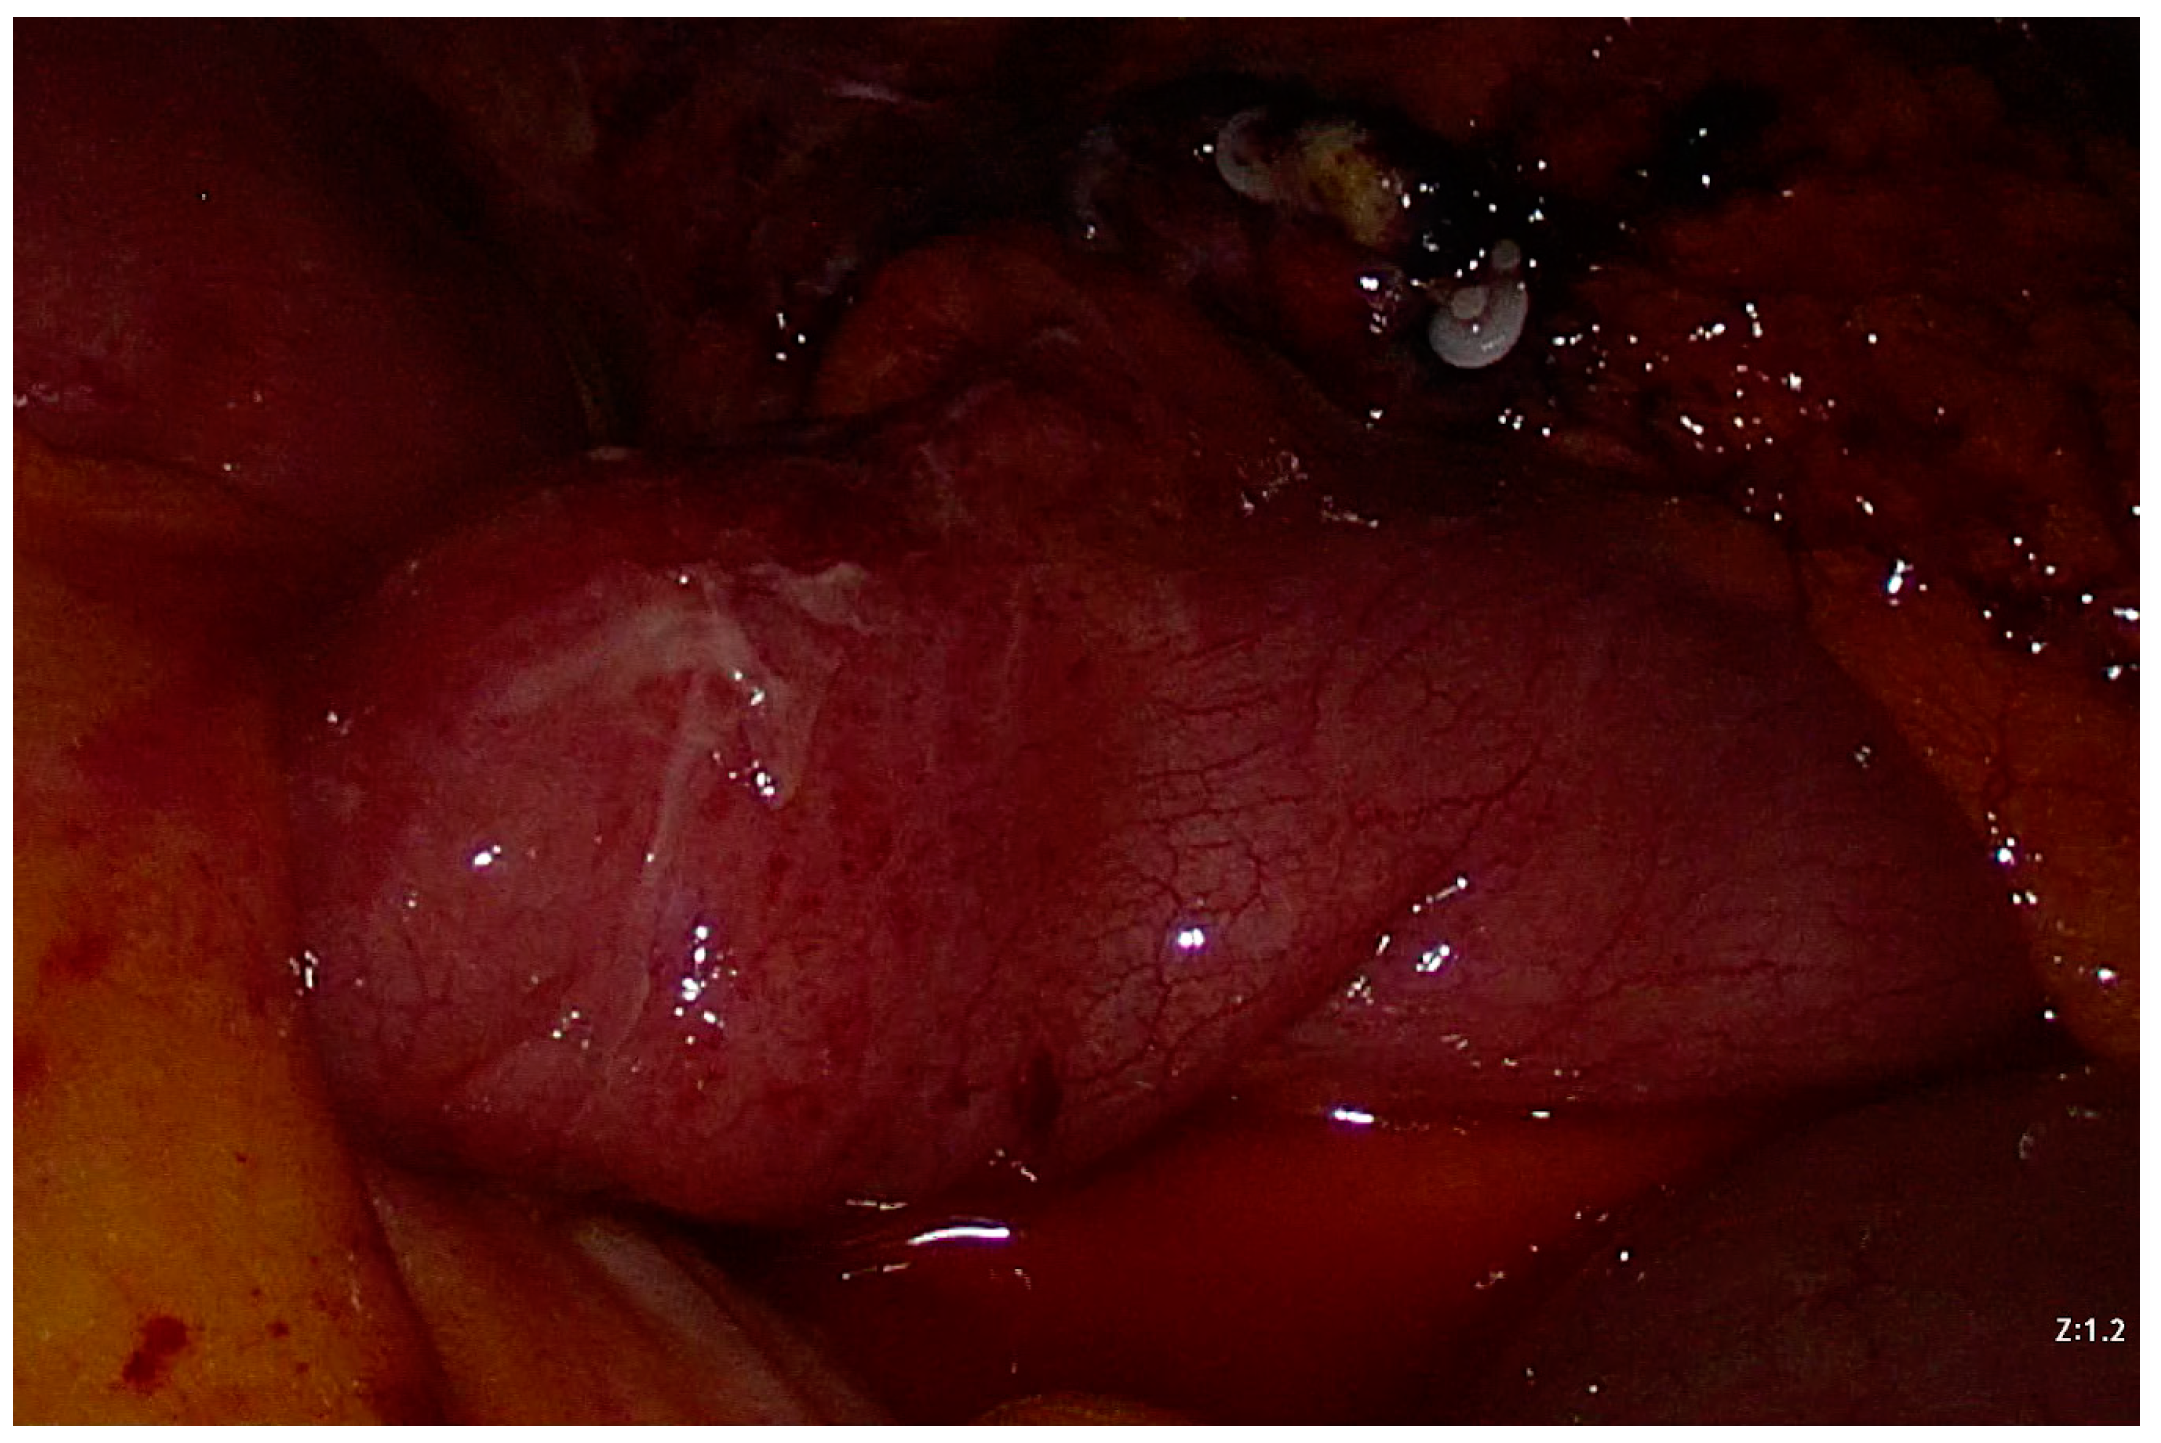

2. Case Presentation